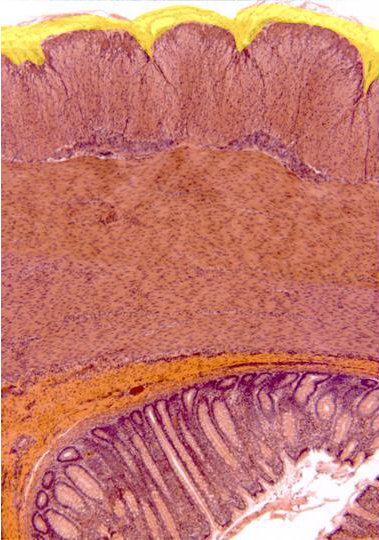

Photographic reconstruction of the intestine wall observed

with the objective of 10x. Going from outside inwards we can

see the following layers:

serous (yellow),

external

and

internal muscular,

submucous

mucous.

The last one contains numerous crypts of Lieberkühn in

contact with the

intestinal lumen.

Between both muscular layers we can notice some

nervous ganglia,

corresponding to the

Auerbach's plexus.